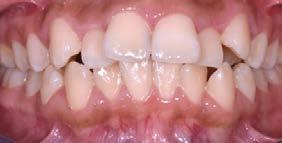

Introducción: el disilicato de litio y el zirconio son de los mejores materiales cerámicos que ofrecen la estética ideal del sector anterior, para la exigencia de los pacientes. Llevar a cabo una correcta toma de color, establecer buena comunicación con el laboratorio y la fase del cementado son factores que buscan lograr un excelente mimetismo con los dientes naturales. Identificar entre estos 2 materiales, cuál ofrece una mejor calidad del color y logrará cumplir los estándares que pide el paciente es crucial. Objetivo: analizar la colorimetría entre 2 materiales cerámicos disilicato de litio y zirconio mediante un reporte de caso clínico. Metodología: experimental comparativo, observacional in vivo en paciente femenino de 56 años, rehabilitado con coronas totales en el sector anterior superior, lado izquierdo con zirconio y lado derecho con disilicato de litio, cementadas con multilink

translucido Ivoclar. Su valoración fue realizada mediante fotografías intraorales con contrastadores negros, en formato RAW, empleando la herramienta de gotero de Adobe Photoshop para la medición del color de ambos cuadrantes superiores. Resultados: las coronas, al ser cementadas, las que fueron confeccionadas con disilicato de litio reportaron tener menos variación del color y el incisivo central reportó menos irregularidad, contra las realizadas de zirconio. Conclusiones: a pesar de usar 2 materiales diferentes, los resultados entre estos son poco significativos. El tener interacción con el paciente sobre el tono deseado final y ser minucioso para el registro del color, serán pasos fundamentales para lograr un buen mimetismo.

Estudio comparativo, observacional y experimental in vivo. Se empleó en una paciente femenina de 56 años de edad; valorada en la clínica de rehabilitación oral del Centro de Estudios Multidisciplinario de Rehabilitación Oral, (CEMRO), en Tarímbaro, Michoacán; quién decidió hacer un cambio en su sonrisa debido a que esta le generaba insatisfacción, cambiando sus restauraciones antiguas, deficientes en el sector anterior; para lo cual se planeó el retiro de 5 coronas de metal-porcelana de los OD 11,12, 13, 21 y 22 vitales, las cuales serán confeccionadas mediante técnica CAD/CAM realizando su historia clínica y autorizando su consentimiento informado.

Se planteó la utilización de cerámica feldespática e-max de la casa comercial Ivoclar Vivadent, en la presentación de bloques para la realización de las coronas totales en los OD

11, 12 y 13 mediante técnica CAD/ CAM, en su versión HT, color A2. Por otro lado, las otras 2 coronas de los OD 21 y 22 fueron confeccionadas con disco de zirconia Zahndent en tono A2. Estas fueron puestas a prueba mediante la aplicación Adobe Photoshop, con ayuda de una fotografía de las coronas tomada antes de su cementación definitiva, y una segunda medición con las coronas ya cementadas, únicamente se realizó el análisis en los OD 11 Y 21, los cuales fueron cementados con cemento translucido Multilink Speed de Ivoclar Vivadent, se tomaron fotografías con cámara profesional Cannon T8 y lente macro 100mm. Es importante mencionar que decidí utilizar cemento dual translucido para evitar alteración en el color de las coronas ya cementadas, con el fin de obtener mediciones puntuales de color y determinar las cantidades de pigmento que hay en cada corona mediante un fondo negro y así poder corroborar que se logró un buen mimetismo. El tiempo estimado para el procedimiento fue de 5 citas.

Figura 1. Coronas antes de su cementación (Francisco Javier Méndez Landa 2024).

porcentaje de 0 a 100, obteniendo el porcentaje exacto de cada uno de esos colores, que una vez mezclados obtenemos el tono real de las coronas (Figura 1).

Se realizó la medición del color de las coronas mediante una fotografía en formato RAW en fondo negro (Figura 2).

Se muestra un análisis del proceso de medición de color de las coronas antes de su cementación y cómo se obtuvieron los resultados, mediante la aplicación Adobe Photoshop (Figura 3).

Se muestra una fotografía del análisis de los incisivos centrales, los cuales fueron confeccionados: el órgano

dentario 11 con disilicato de litio y el órgano dentario 21 con zirconio.

Figura 3. Coronas ya cementadas.